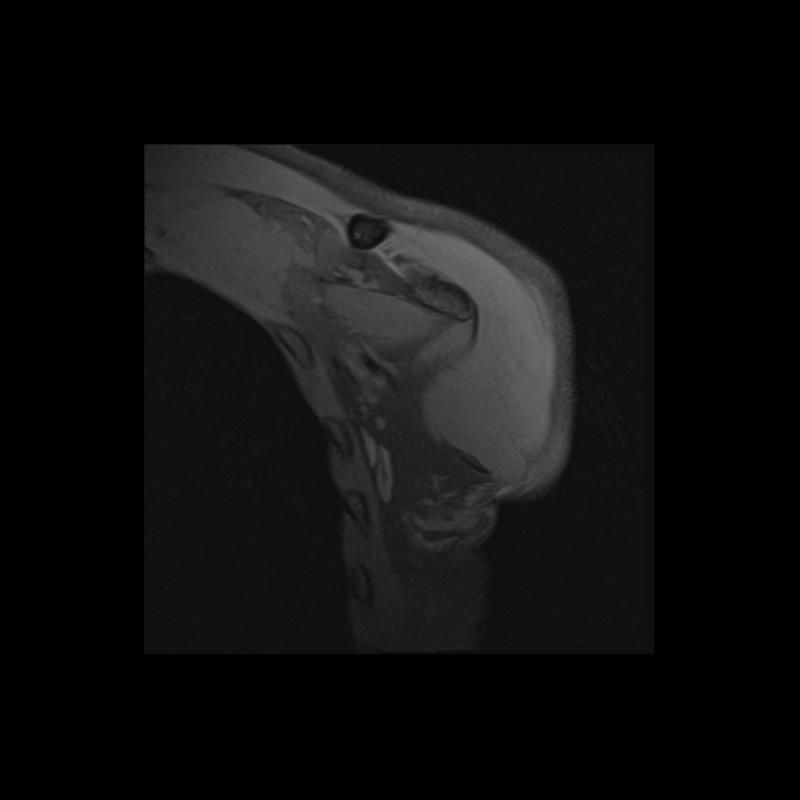

Shoulder MRI Anatomy